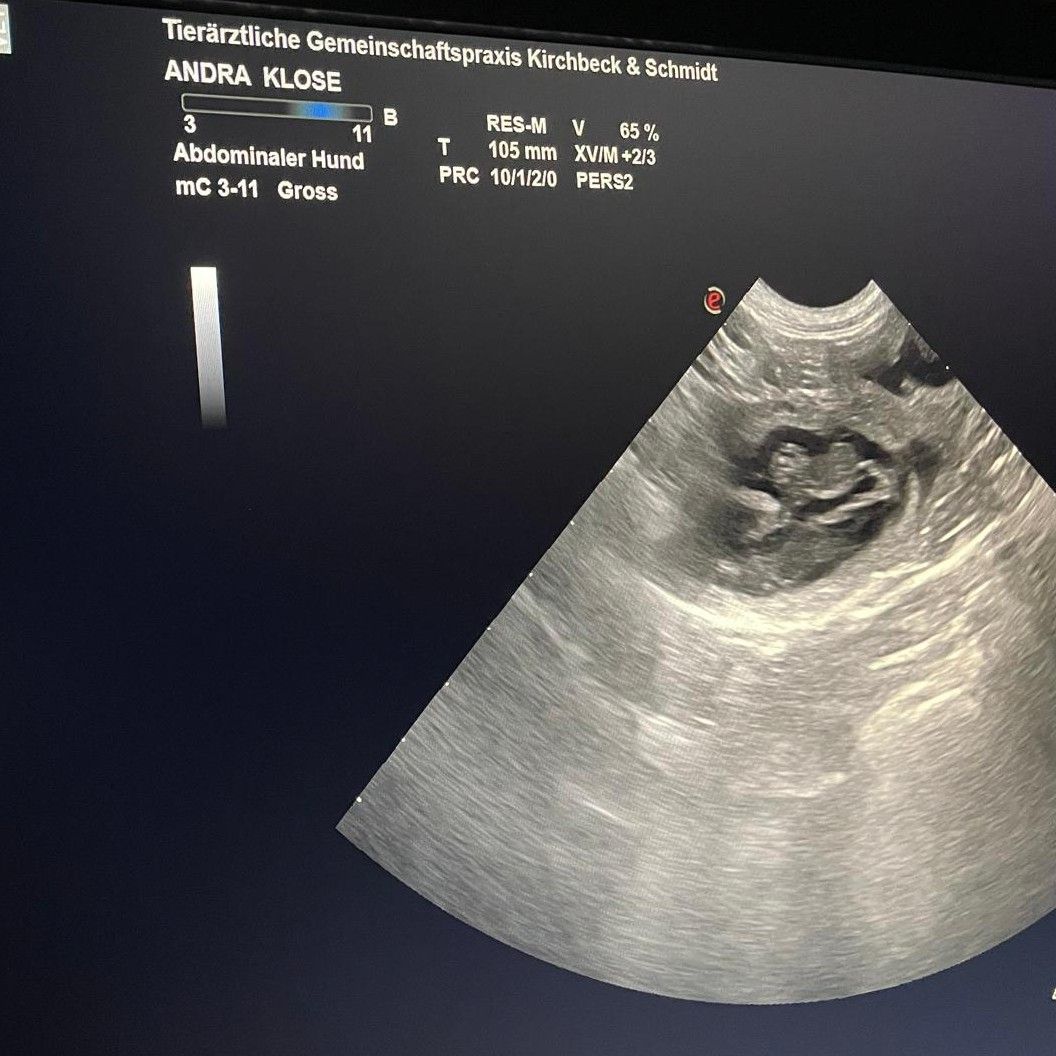

Heute war der Ultraschalltermin... und es wurden eine Welpenschar gesichtet. Wir drücken die Daumen für eine entspannte weitere Schwangerschaft und ebenso entspannte Geburt mit süßen, gesunden Welpen. Es können alle Farben fallen! Es fielen 4 Rüden und 3 Hündinnen in allen Farben! Herzlichen Glückwunsch!!